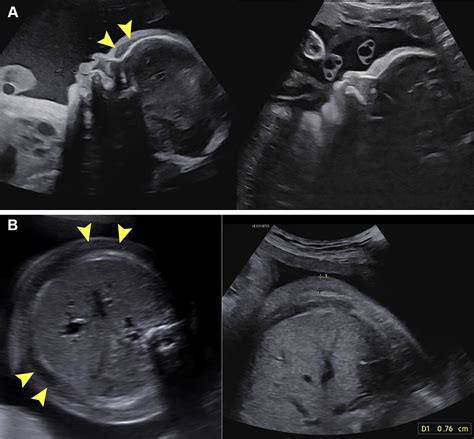

• Ultrasound: Ultrasound examinations are the most common method for detecting fetal edema. They can reveal fluid accumulation in the fetal tissues and body cavities.

• Abnormal Ultrasound Findings: Ultrasound examinations may reveal fluid accumulation in the fetal tissues or body cavities.